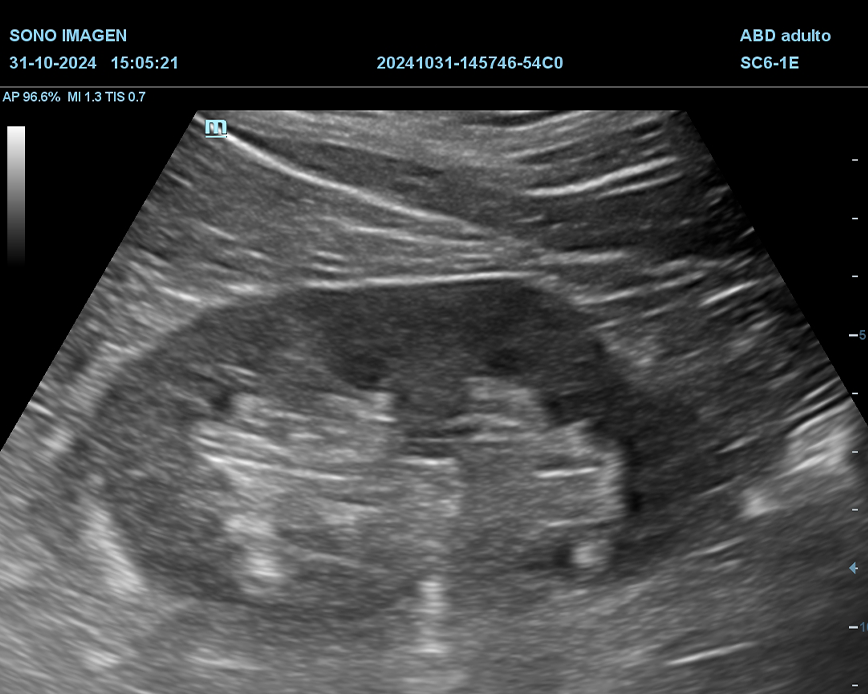

Ecografía Prostática

- hiperplasia prostática benigna(HPB)

- cáncer de próstata

- prostatitis

- dificultad para orinar o retención urinaria

- hematuria

- alteraciones en la fertilidad masculina

- control postquirúrgico o postratamiento

- anomalías detectadas en estudios previos

- quistes prostáticos